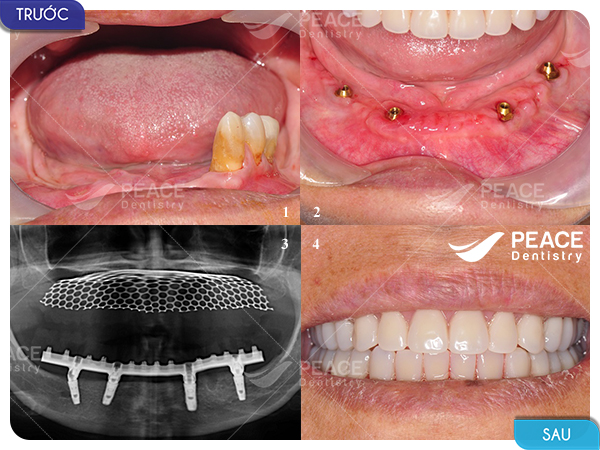

Hình ảnh thực tế